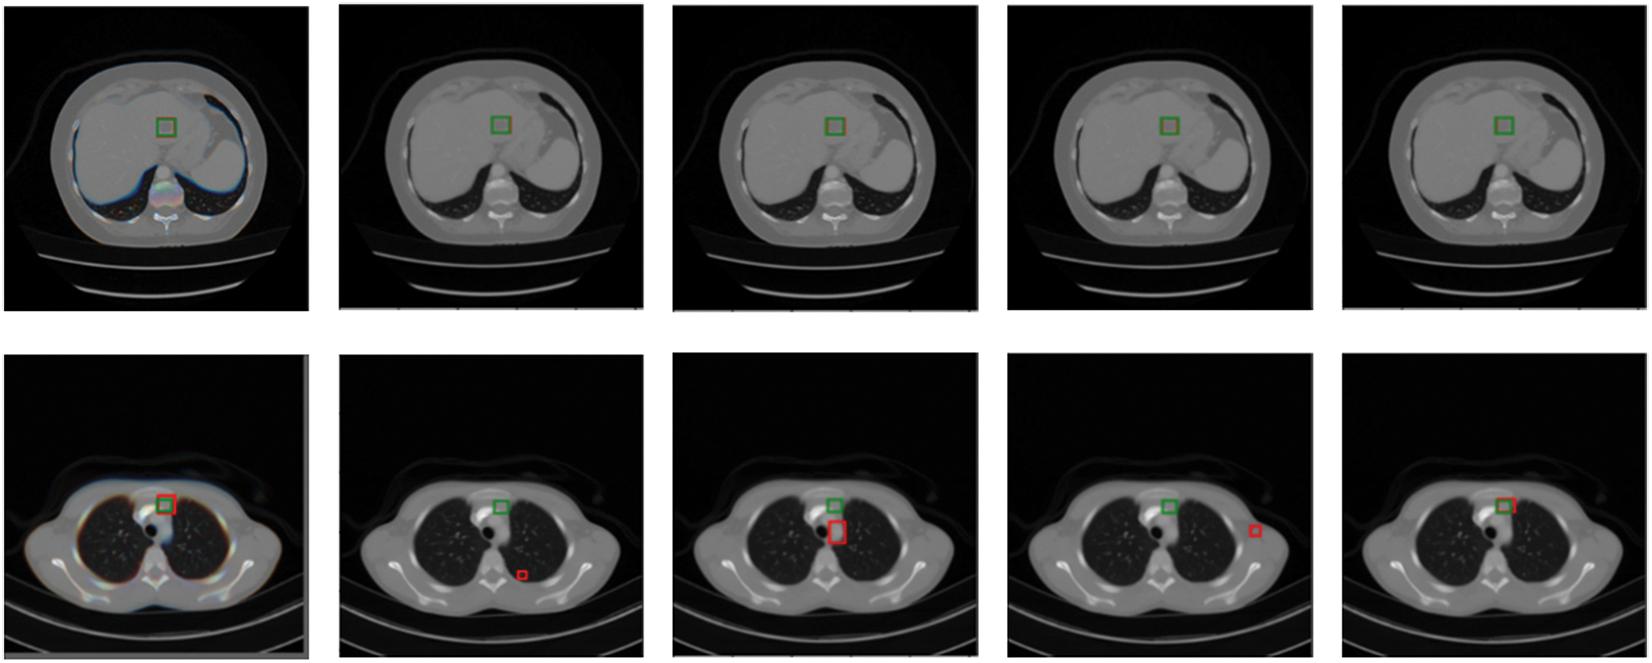

Predicted bounding boxes generated from several compared models are illustrated in Fig. 5. Our model shows superior capability to predict both the lesion location and size when compared with other methods. It is evident that the proposed method enhances the performance in detecting very small-sized or larger lesions. However, the insufficient training data for certain organ lesions resulted in inadequate generalization for the detection of these lesions as can be seen in Fig. 6.

Figure 5: Qualitative comparison of several existing universal lesion detection models and ours on the testing set of DeepLesion. Green and red boxes correspond to ground-truths in the test set and predicted true positives